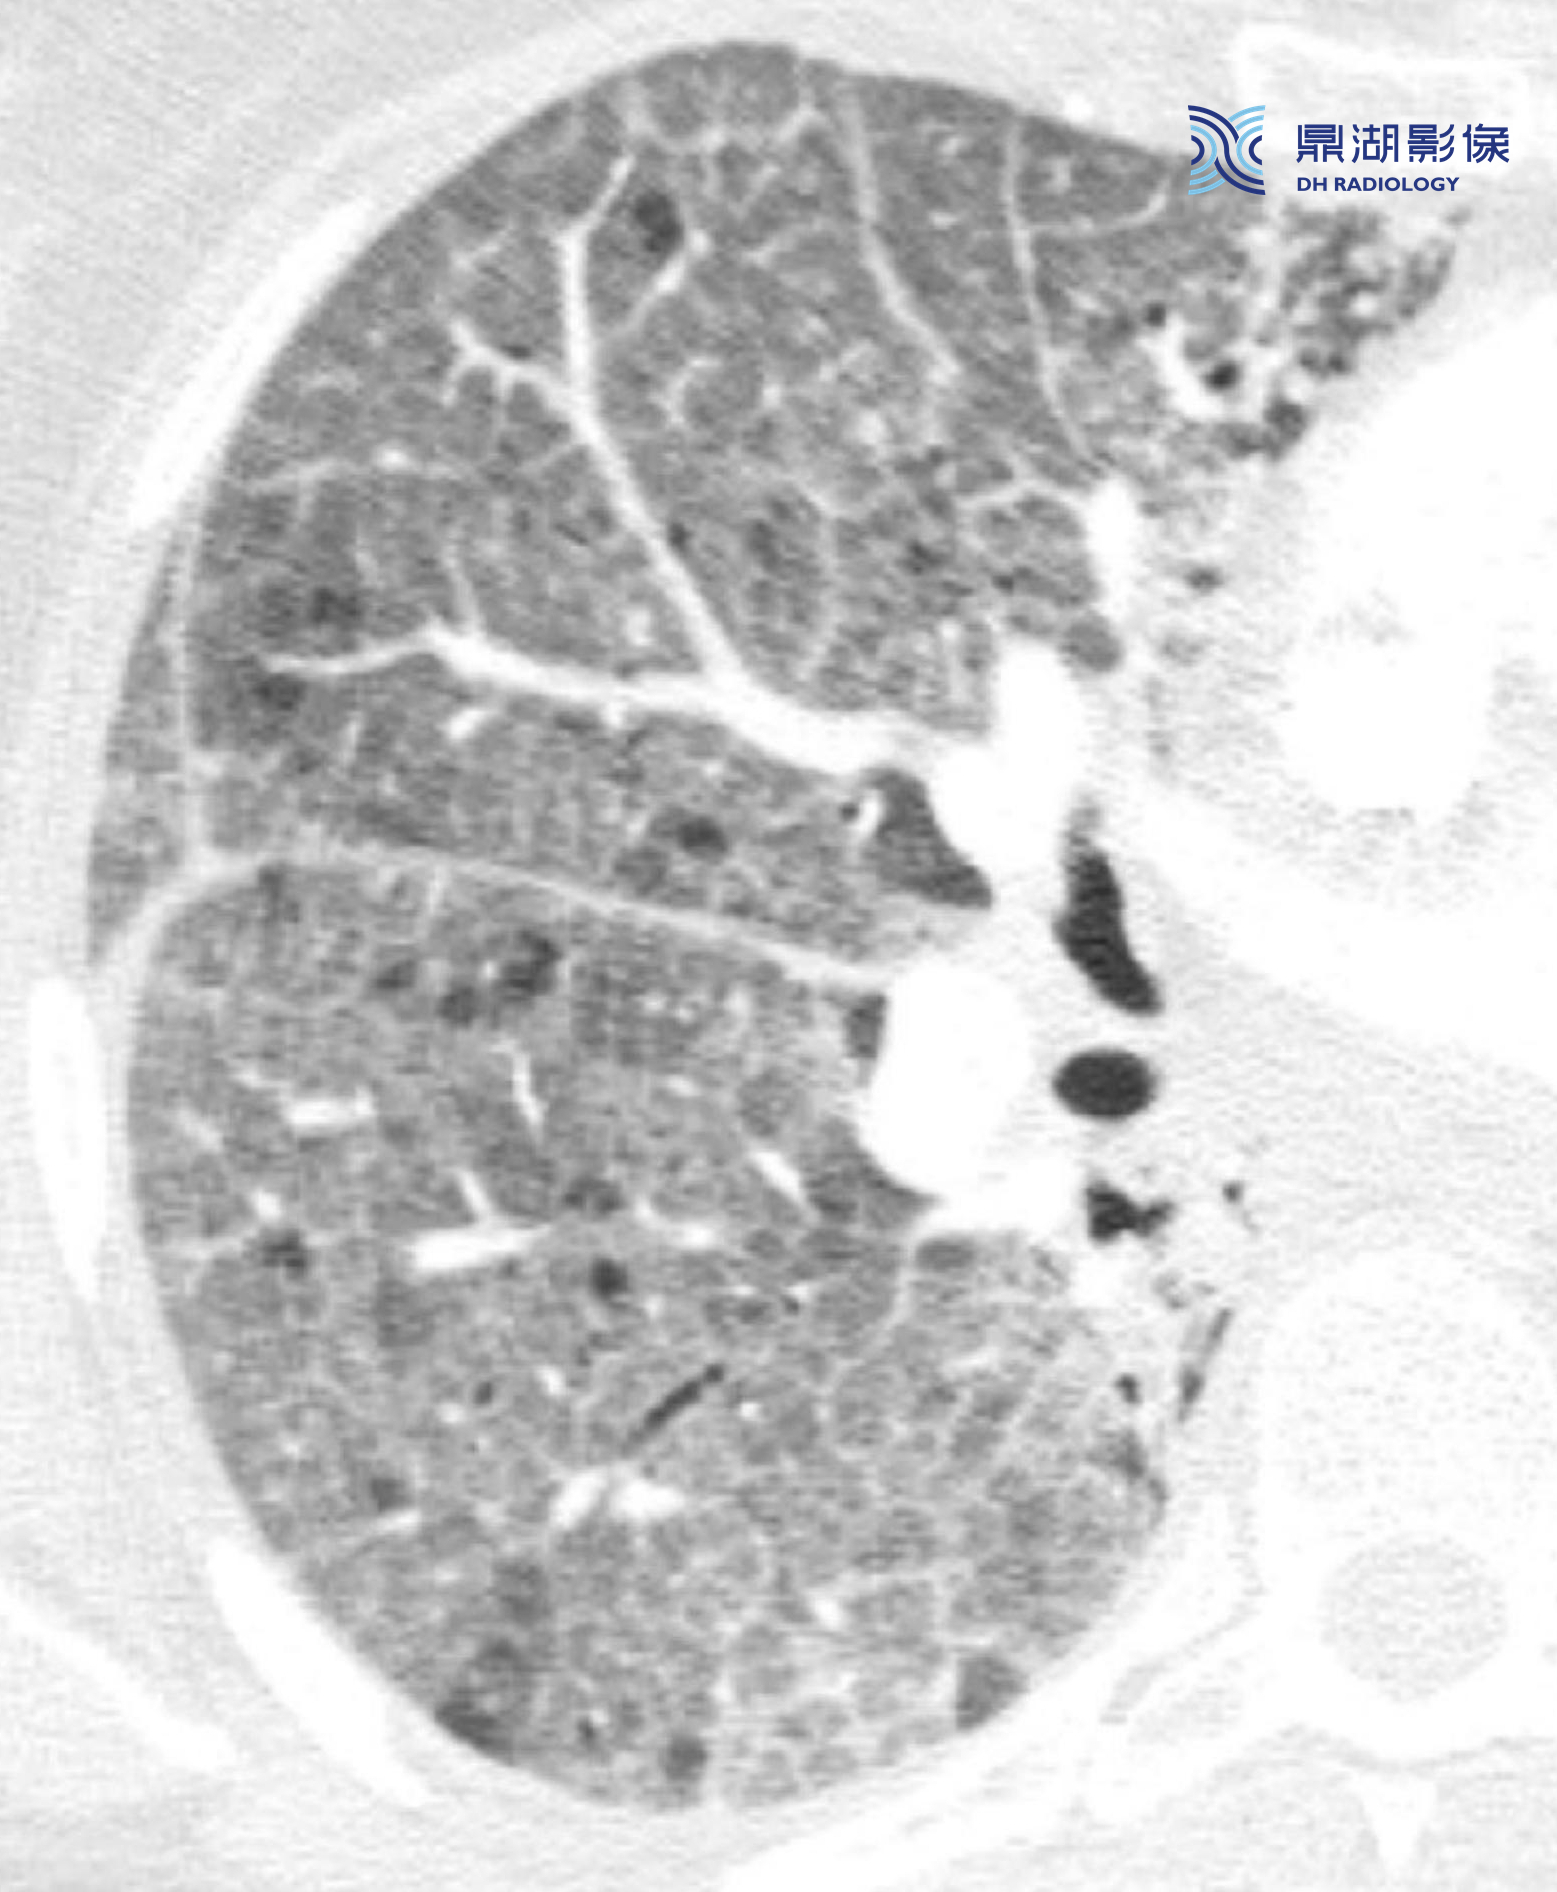

20d11bbae20d111476bb8d5e7b7b98ac.png

865b77b4654914c49e88ae84b97e9134.png

弥漫性肺泡损伤导致的急性呼吸窘迫综合征(ARDS)的典型表现。本例为败血症患者,HRCT显示弥漫性实变和GGO,虽然为非特异性,却是DAD和ARDS的典型表现。

注意:肺外周和肺下垂区受累更为严重。